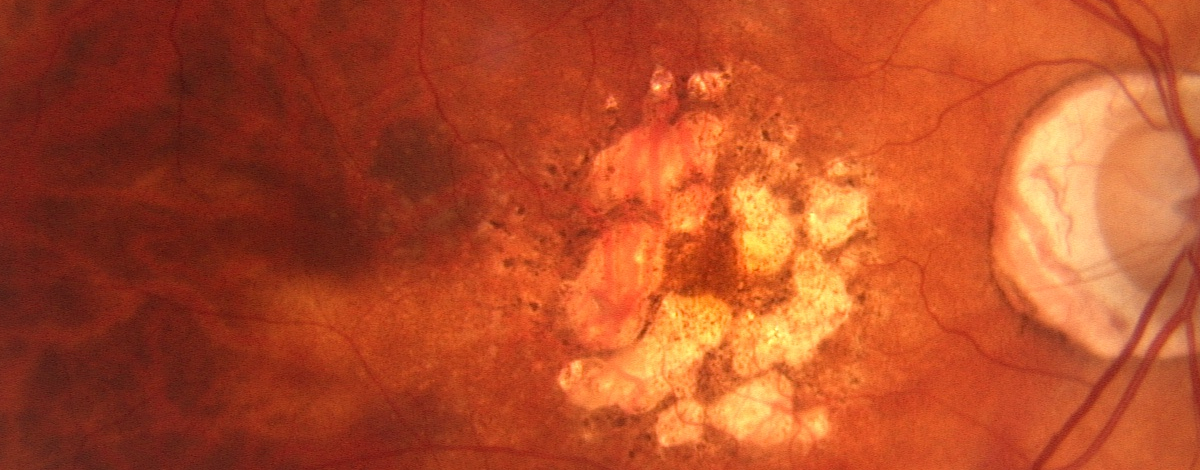

La DMLE umida si caratterizza per la crescita di neovasi sanguigni con pareti molto fragili, che lasciano filtrare fluido e sangue nella macula. La perdita di vista è molto rapida

La DMLE umida viene controllata con iniezioni nel corpo vitreo di farmaci antiangiogenici che frenano la crescita dei vasi sanguigni anomali.